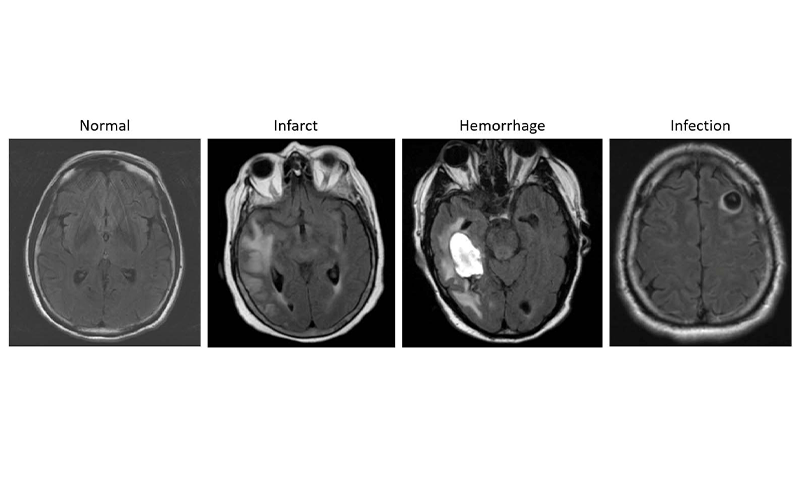

Study Demonstrates Ability to Differentiate Normal Vs. Abnormal Exams

In preliminary testing, the model showed relatively good performance to differentiate likely normal or likely abnormal examinations. Testing on a validation dataset acquired at a different time period and from a different institution than the data used to train the algorithm highlighted the generalization capacity of the model. Such a system could be used as a triage tool, according to Dr. Gauriau, with the potential to improve radiology workflow.

The work was the first of its kind to leverage a large and clinically relevant dataset and use full volume MRI data to detect overall brain abnormality. The next steps in the research include evaluating the model’s clinical utility and potential value for radiologists. Researchers would also like to develop it beyond the binary outputs of “likely normal” or “likely abnormal.”

“This way we could not only have binary results but maybe something to better characterize the types of findings, for instance, if the abnormality is more likely to be related to tumor or to inflammation,” Dr. Gauriau said. “It could also be very useful for educational purposes.”